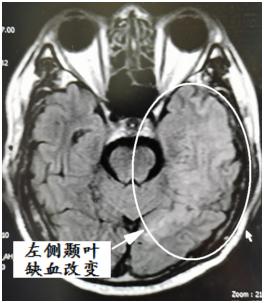

患者白某,男,68岁,汉族,因“突发言语不清5小时”于2021年1月28日 16:37以“急性脑血管病”就诊于我院急诊科。急诊完善颅脑CT未见出血,考虑急性脑梗死,由于错过了静脉溶栓治疗时间窗,准备于导管室取栓治疗,但完善脑血管造影后发现患者并非急性脑栓塞病变,而是硬脑膜动静脉瘘所致。因此为求诊疗精确,于内科保守治疗一周,并远程邀请兰大二院神经外科介入专家张海林教授会诊后确诊为硬脑膜动静脉瘘,并决定于今日行介入下颅脑动静脉瘘栓塞术。

硬脑膜动静脉瘘(dAVF)约占所有颅内血管畸形的10%,是位于硬脑膜内的动脉和静脉系统之间的异常分流,导致静脉压力过高,从而出现颅内脑组织毛细血管血流瘀滞,最终导致缺血性脑梗塞,症状酷似急性缺血性脑梗塞,目前病因仍然不明确。虽然它们可能是良性病变,但存在逆行静脉引流和皮质静脉回流,使这些病变的自然病程具有高出血、神经损伤和死亡的逆袭性的高风险。血管内治疗通常是dAVF的一线治疗,主要方法包括栓塞瘘的连接处及其静脉成分。